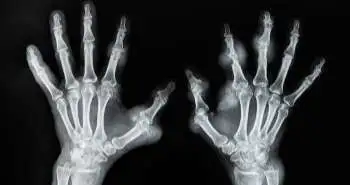

Рівень сечової кислоти при надходженні до відділення ГД становив 10,8 мг/дл (642 мкмоль/л). На рентгенограмах кистей були виявлені остеопенія, ерозії та кілька літичних вогнищ у променевій та ліктьовій кістках, а також кістках зап'ястя, разом із великими об'ємними утвореннями з м'яких тканин. Усі ці прояви вказували на наявність важкої двосторонньої подагри без ознак відкладення пірофосфату кальцію або інших артропатій.